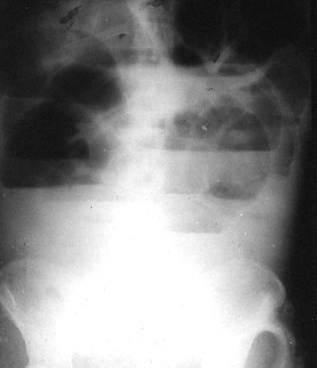

术中证实乙状结肠扭转,扭转360度,完全性接肠梗阻,乙状结肠扩

大肠梗阻